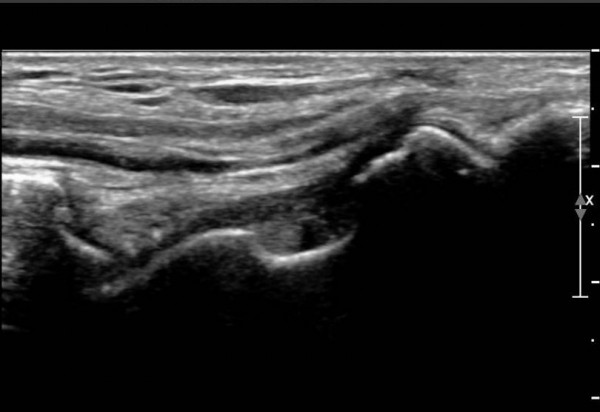

¾Õ°æ°ñºñ°ñÀδë Á¾´Ü¸é°Ë»ç¿¡¼­ °æ°ñºñ°ñÀδëÀÇ  Àú¿¡ÄÚ  ºÎÁ¾ ¹× ÀδëºÎÂøºÎ °æ°ñÀÇ

°ß¿­°ñÀýÀÌ  °üÂûµÊ(»çÁø 2, 3, 4)